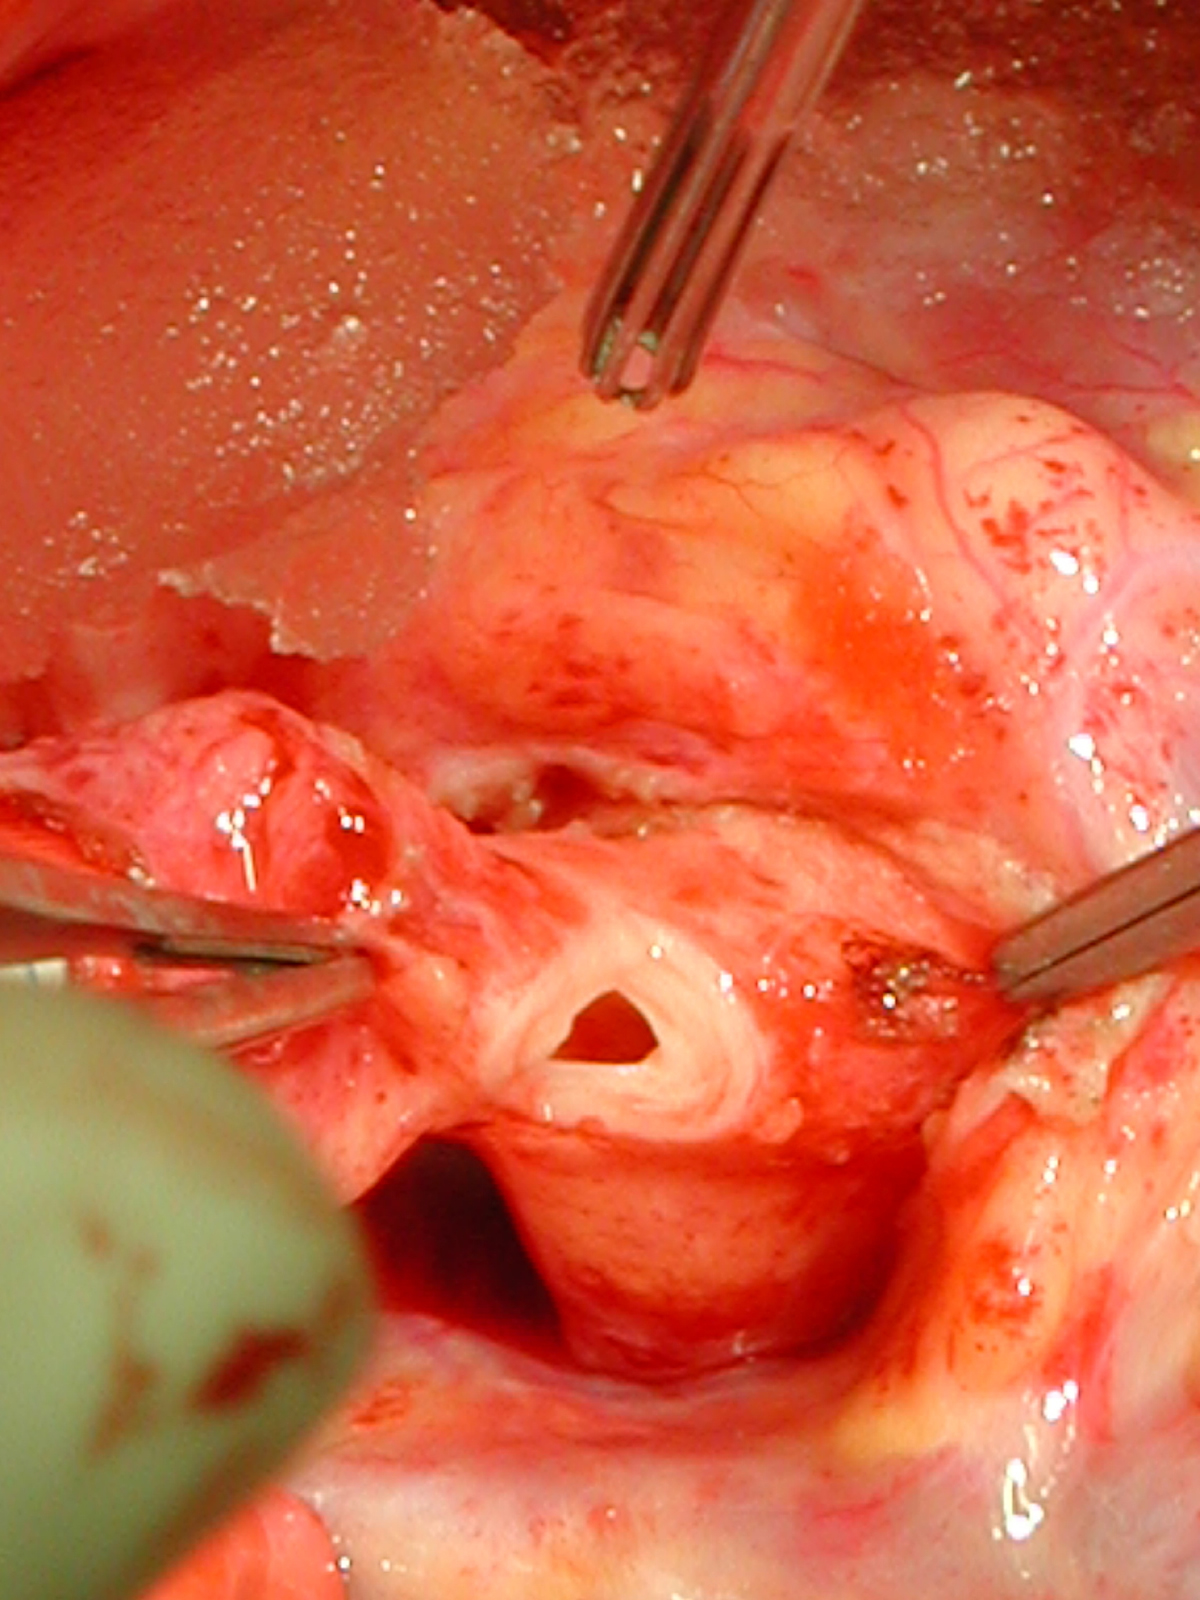

The operative approach is through a median sternotomy with the use of cardiopulmonary bypass and bicaval venous cannulation. The first dose of cold blood cardioplegia is antegrade; the remaining doses are retrograde.

High ascending aortic cannulation adjacent to the innominate artery for maximum exposure of the ascending aorta and to allow length for positioning of the patch in the ascending aorta.

First coronary sinus incision in noncoronary sinus to facilitate exposure of the incisions into the coronary orifice sinuses.

In most cases, the right coronary artery sinus should be opened to the left of the coronary orifice and the left coronary artery sinus to the right of the coronary orifice. Occasionally one may not have enough room between a coronary orifice and the aortic valve; in this case the incision site should be tailored to the situation.

Ensure similar orifice sizes between the proximal and distal ascending aorta after patch augmentation by the use of a sizing dilator.